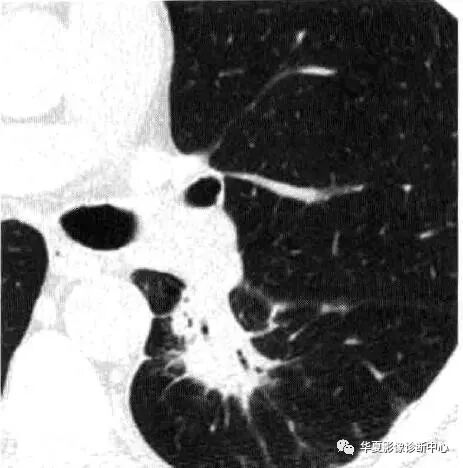

在边缘特征方面,CT上恶性结节更可能表现为边界不清、轮廓不规则、分叶、毛刺边缘。良性病变一般具有光滑、锐利的边缘。近90%边缘不规则或有毛刺的结节是恶性;仅有20%边缘光滑 锐利的结节是恶性。

在结节形态上,肺癌往往形态不规则,呈分叶状、锯齿状,但很少有边缘凹陷。肉芽肿(良性增生)常是圆形的,错构瘤和转移瘤(良性瘤子)可能是圆形、椭圆形或分叶状,瘢痕、肺不张或瘢痕化区域可能会出现直线或成角。